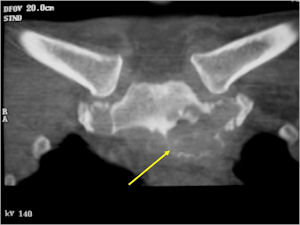

Sites:

- Spine (40% of cases; usually posterior elements)

CT Scan:

- More useful for detecting mineralization and evaluating extent of bone destruction than plain X-ray